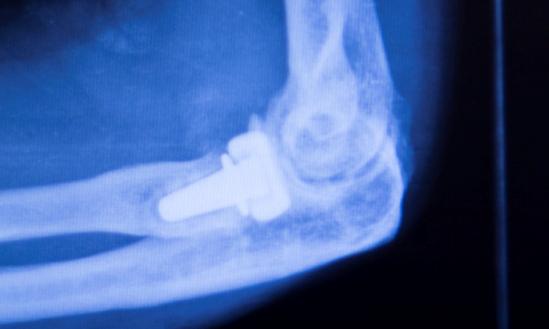

骨科植入器材是指被植入人体内,用于取代、修复、补充、填充或辅助治疗受损伤骨骼的器材的统称。它们主要由金属材料、生物陶瓷材料、高分子材料等制成,可以长期植入人体,对人体的生命和健康有着重大影响。骨科植入......

骨科植入医疗器械,指的是通过手术植入人体,可以起到替代、支撑人体骨骼或者可以定位修复骨骼、关节、软骨等组织的器材材料,主要包括骨接合植入物及关节植入物,如接骨板、接骨螺钉、髓内钉、脊柱内固定植入物、人......